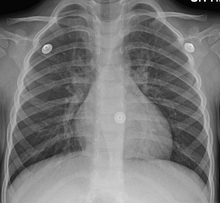

In more than 90% of cases the cause is a viral infection.[2] These viruses may be spread through the air when people cough or by direct contact. Risk factors include exposure to tobacco smoke, dust, and other air pollution.[1] A small number of cases are due to high levels of air pollution or bacteria such as Mycoplasma pneumoniae or Bordetella pertussis.[2][4] Diagnosis is typically based on a person's signs and symptom.[5] The color of the sputum does not indicate if the infection is viral or bacterial. Determining the underlying organism is typically not needed.[2] Other causes of similar symptoms include asthma, pneumonia, bronchiolitis, bronchiectasis, and COPD.[2][6] A chest X-ray may be useful to detect pneumonia.[2]

- A chest X-ray is useful to exclude pneumonia which is more common in those with a fever, fast heart rate, fast respiratory rate, or who are old.[6]